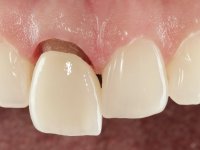

A pre-print was performed to make a crown in dual-cured resin. After a cross-section with a turbine, the infiltrated crown was removed with a microluxador. The dental stump was re-prepared to better define the shape and location of the cervical margin. It was necessary to place composite resin on the buccal surface of the provisional crown to improve its esthetics. The impression was made using a double-mix technique with two-viscosity, quick-setting silicones. In the laboratory, a crown with a ceramic-coated Zr infrastructure was made. After placing it in the mouth, we verified that the crown showed a greater translucency than the symmetrical one, not fulfilling our aesthetic goals. The ceramist had the opportunity to observe the situation in the clinic, collecting records for later rectification. The new crown was placed in the mouth and approved by the patient. The final cementation was done with resin-reinforced glass ionomer cement.